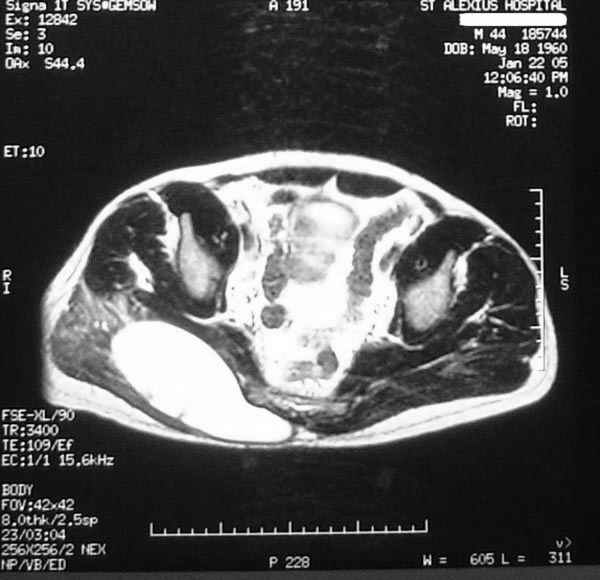

Уважаемые коллеги,Неоднократные пункционные эвакуация (3 раза) крови изягодичной области, после полученной пройзводственнойтравмы (более 1.5 мес) ударом в ягодицу тяжелым, около полутонны предметом.

Рентгенограмма без особенностей, несмещенные переломы лонной и седалищных костей таза.Последная пункция 10 дней назад 180 мл темной крови, после пункции сделано магнито-резонансные исследование (на снимках), какой диагноз и тактика дальнейшего лечения, какие рекомендации?Джолдас Кульджанов

Djoldas Kuldjanov, M.D. 06 Март 2005, 00:25

Разбираемый случай немного отличался от классического Degloving Injury

или Morel-Lavalle Lesion, которые часты при переломах ацетабулума и

костей таза. Состояние, наблюдаемое после удара, в результате чего

образуются обширные полости в тазобедренной области: ягодицы или

большого вертела. Как описал Анатолий, обширные полости заполняются

кровью, затем синовиальной жидкостью, отодвигают сроки операции или

после операции приводят к осложнениям послеоперационных ран.

Описанный случай:

В промежутке около месяца 3 пункции с удалением около 180 мл крови

каждый раз. После исследовании МРТ было принято решение - удаление

гематомы в операционной более широким доступом. Во время операции -

под ягодичной мышцей была капсула, где скопилось около 700 мл

гематомы, после удаления в полости обнаружили несколько закупорившихся

вен и краевой разрыв одной из двух ветвей нижней ягодичной артерии.

После промывания, гемостаза и дренажа, по рекомендации хирурга стенку

полости обработали спреем Tisseel, специальным склерозирующим

препаратом, применяемым пластическими хирургами, затем зашили рану.

Дренажи удалены на 5 день, рана зажила первично. Случай был интересен

применением препарата Tisseel Fibrin Sealant для склерозирования

полостей, только недавно получившим разрешение к применению, хотя по

аннотации в Европе и в Южной Америке применяют давно.